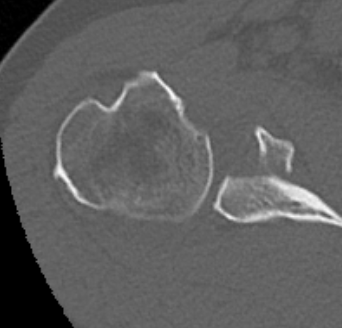

Type IA: Anterior glenoid rim fracture

Xray / CT